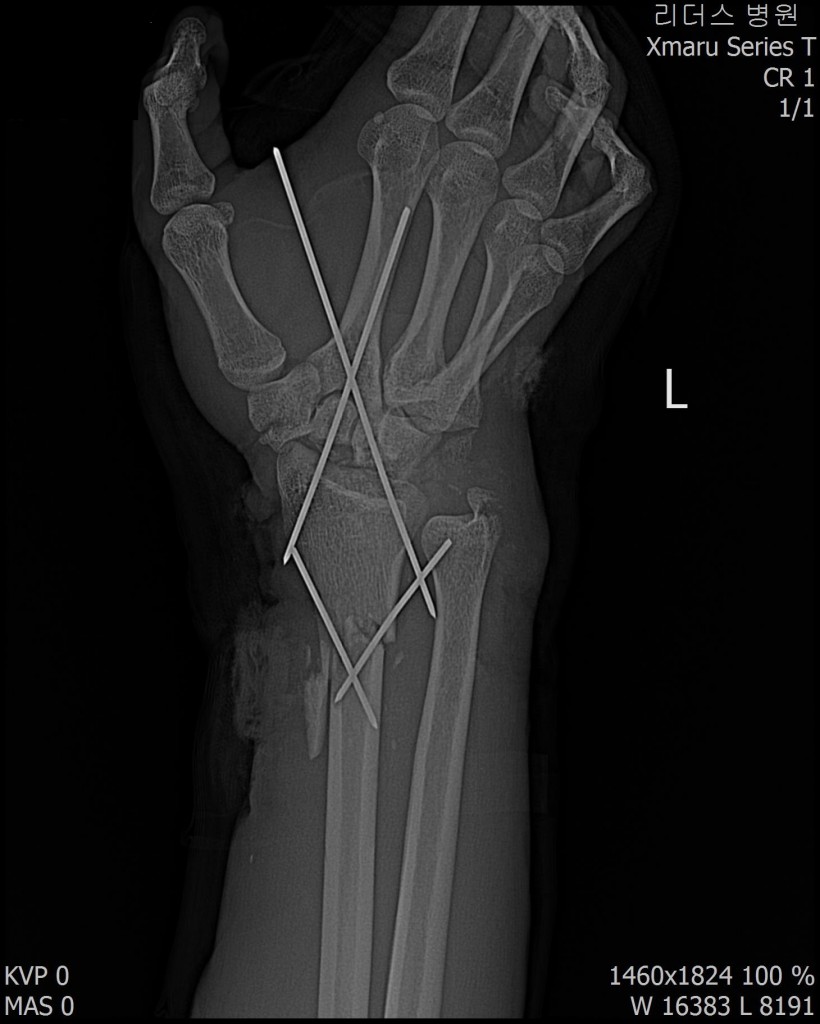

2017년 12월 23일 좌측 손목 절단 ( 치료 과정 모습)

20171223일 당시 ( 외국인 미 **)께서 좌측 손목 전달되어 본원 방문함.

2018.115일 현재 치료 중인 환자에 대하여 .....